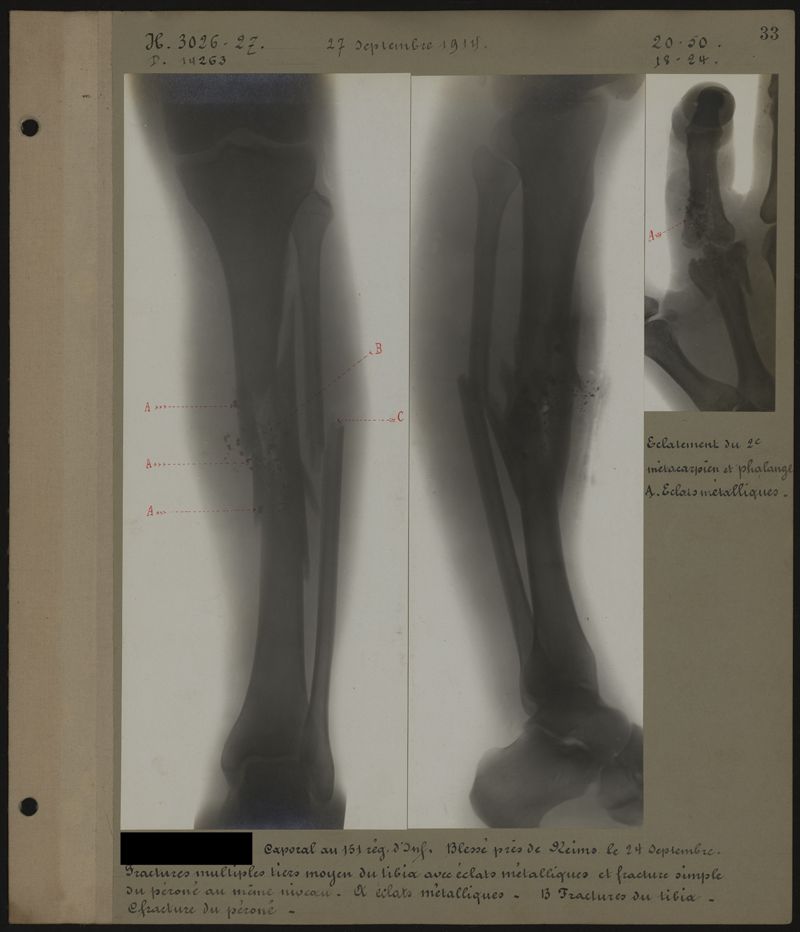

Deux albums de radiographies de la Première Guerre mondiale. Collection du laboratoire central de radiographie de la Salpêtrière. Premier album.

1914.